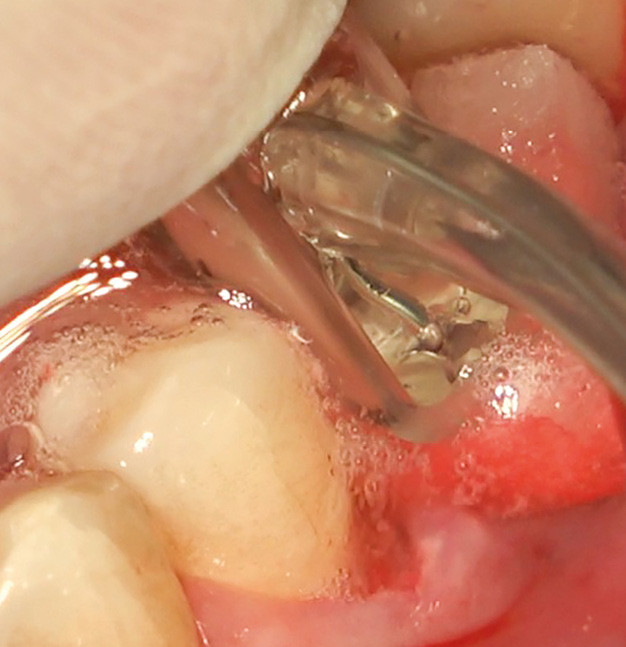

![7, 8 et 9. Un lambeau de pleine épaisseur est levé et le tissu de granulation retiré à l’aide d’une mini curette en titane. Nous observons un défaut osseux combiné de type I et II, avec une perte osseuse verticale circonférentielle en forme de cratère (très favorable à la régénération) couplée à une perte horizontale au niveau de la paroi vestibulaire [4].](https://www.idwebformation.fr/wp-content/uploads/sites/2/2024/02/712-tt-width-800-height-484-fill-1-crop-0-bgcolor-12181f-post_id-164944-768x465.jpg)